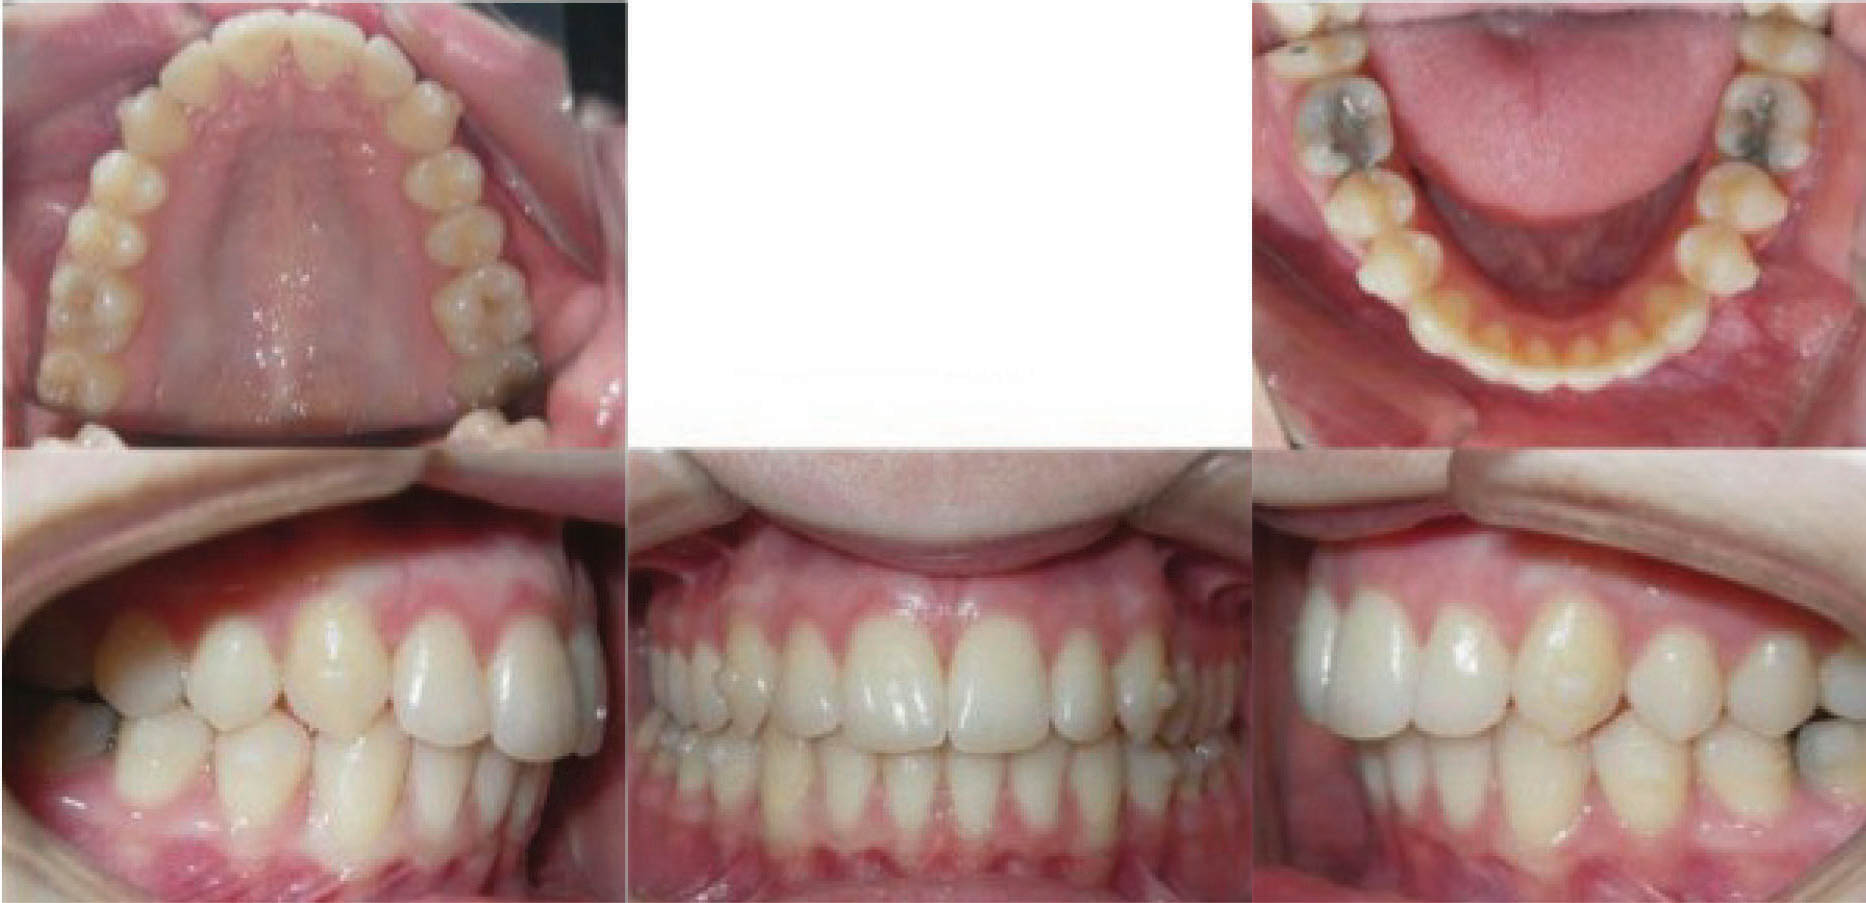

بیمار بعدی یک دختر ۱۶ ساله ClII/1 با اوربایت نرمال و اورجت زیاد است. کرادینگ مختصر دو فک دارد، قوس بالا تنگ، و پروفایل او طبیعی است (شکل 83-۶ الی 85-۶). در این بیمار از الاستیک کلاسII استفاده شده است. الگو اسکلتی طبیعی، رادیوگرافی لترال سفالومتری نشان دهنده دندانهای قدامی پروترود شده بالا با الگو طبیعی اسکلتی میباشد. رادیوگرافی OPG طبیعی است. قسمت بعُد افقی چک لیست را به این نحوه پر کردیم:

از الاستیک کلاسII برای اصلاح رابطه افقی استفاده گردیده است. شروع الاستیک کلاسII بعد از مرتب شدن دندانها بود و از الاستیک ۴ انسی استفاده نمودیم چون میزان اصلاح زیاد بود.

در انتهای درمان (شکلهای 89-۶ الی 91-۶) اکلوژن کلاسI شده است. دندانها مرتب شدند و اوربایت و اورجت طبیعی و به حداکثر زیبایی دست یافتیم. عکس نهایی OPG طبیعی است. مقایسه عکسهای لترال ابتدا و انتهای درمان نشاندهنده تغییر قابل ملاحظه موقعیت انسیزورهای بالا است که منجر به اصلاح اورجت گردیده است. لبخند او عالی گردید.

نتیجه: کل درمان ۲۲ ماه به طول انجامید، 45 الاینر و الاستیک کلاسII ۴ انسی.